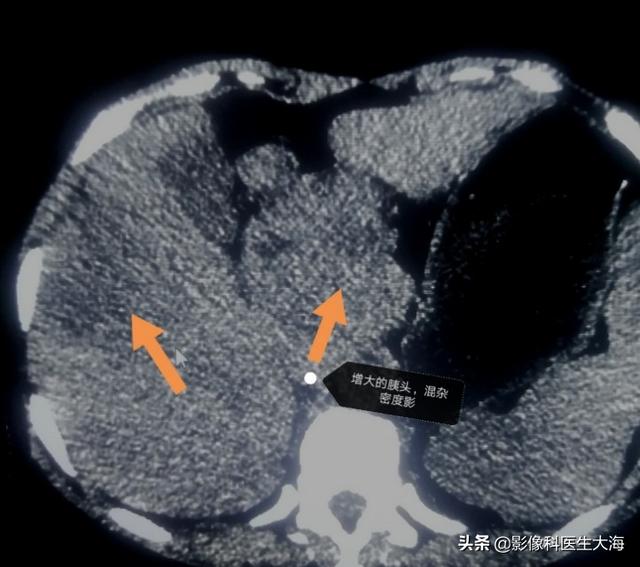

Ich bin Bildgebung Arzt Meer, regelmäßig teilen Gesundheit Wissen, wie plus Aufmerksamkeit Oh!